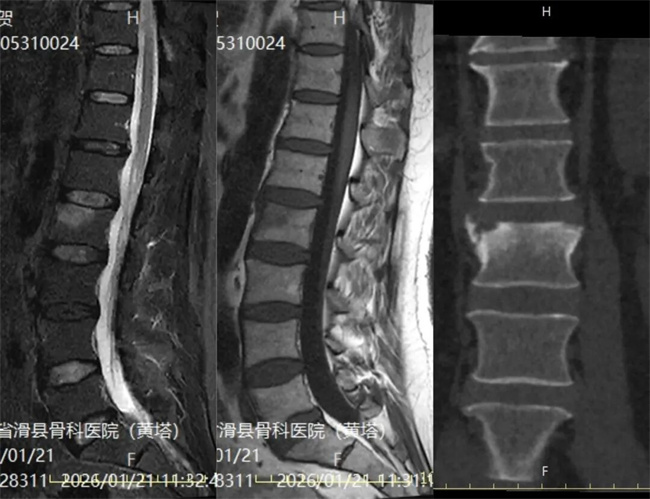

一、患者耿某某,男,49岁,患者腰部僵硬半年余,腰部椎旁肌肉僵硬,腰2椎体压叩疼征阳性。为求进一步治疗,来到我院请专家会诊,通过各位专家会诊查体、查看影像资料并细致认真的分析后,诊断为:低度脊椎感染,意见:定期复查。